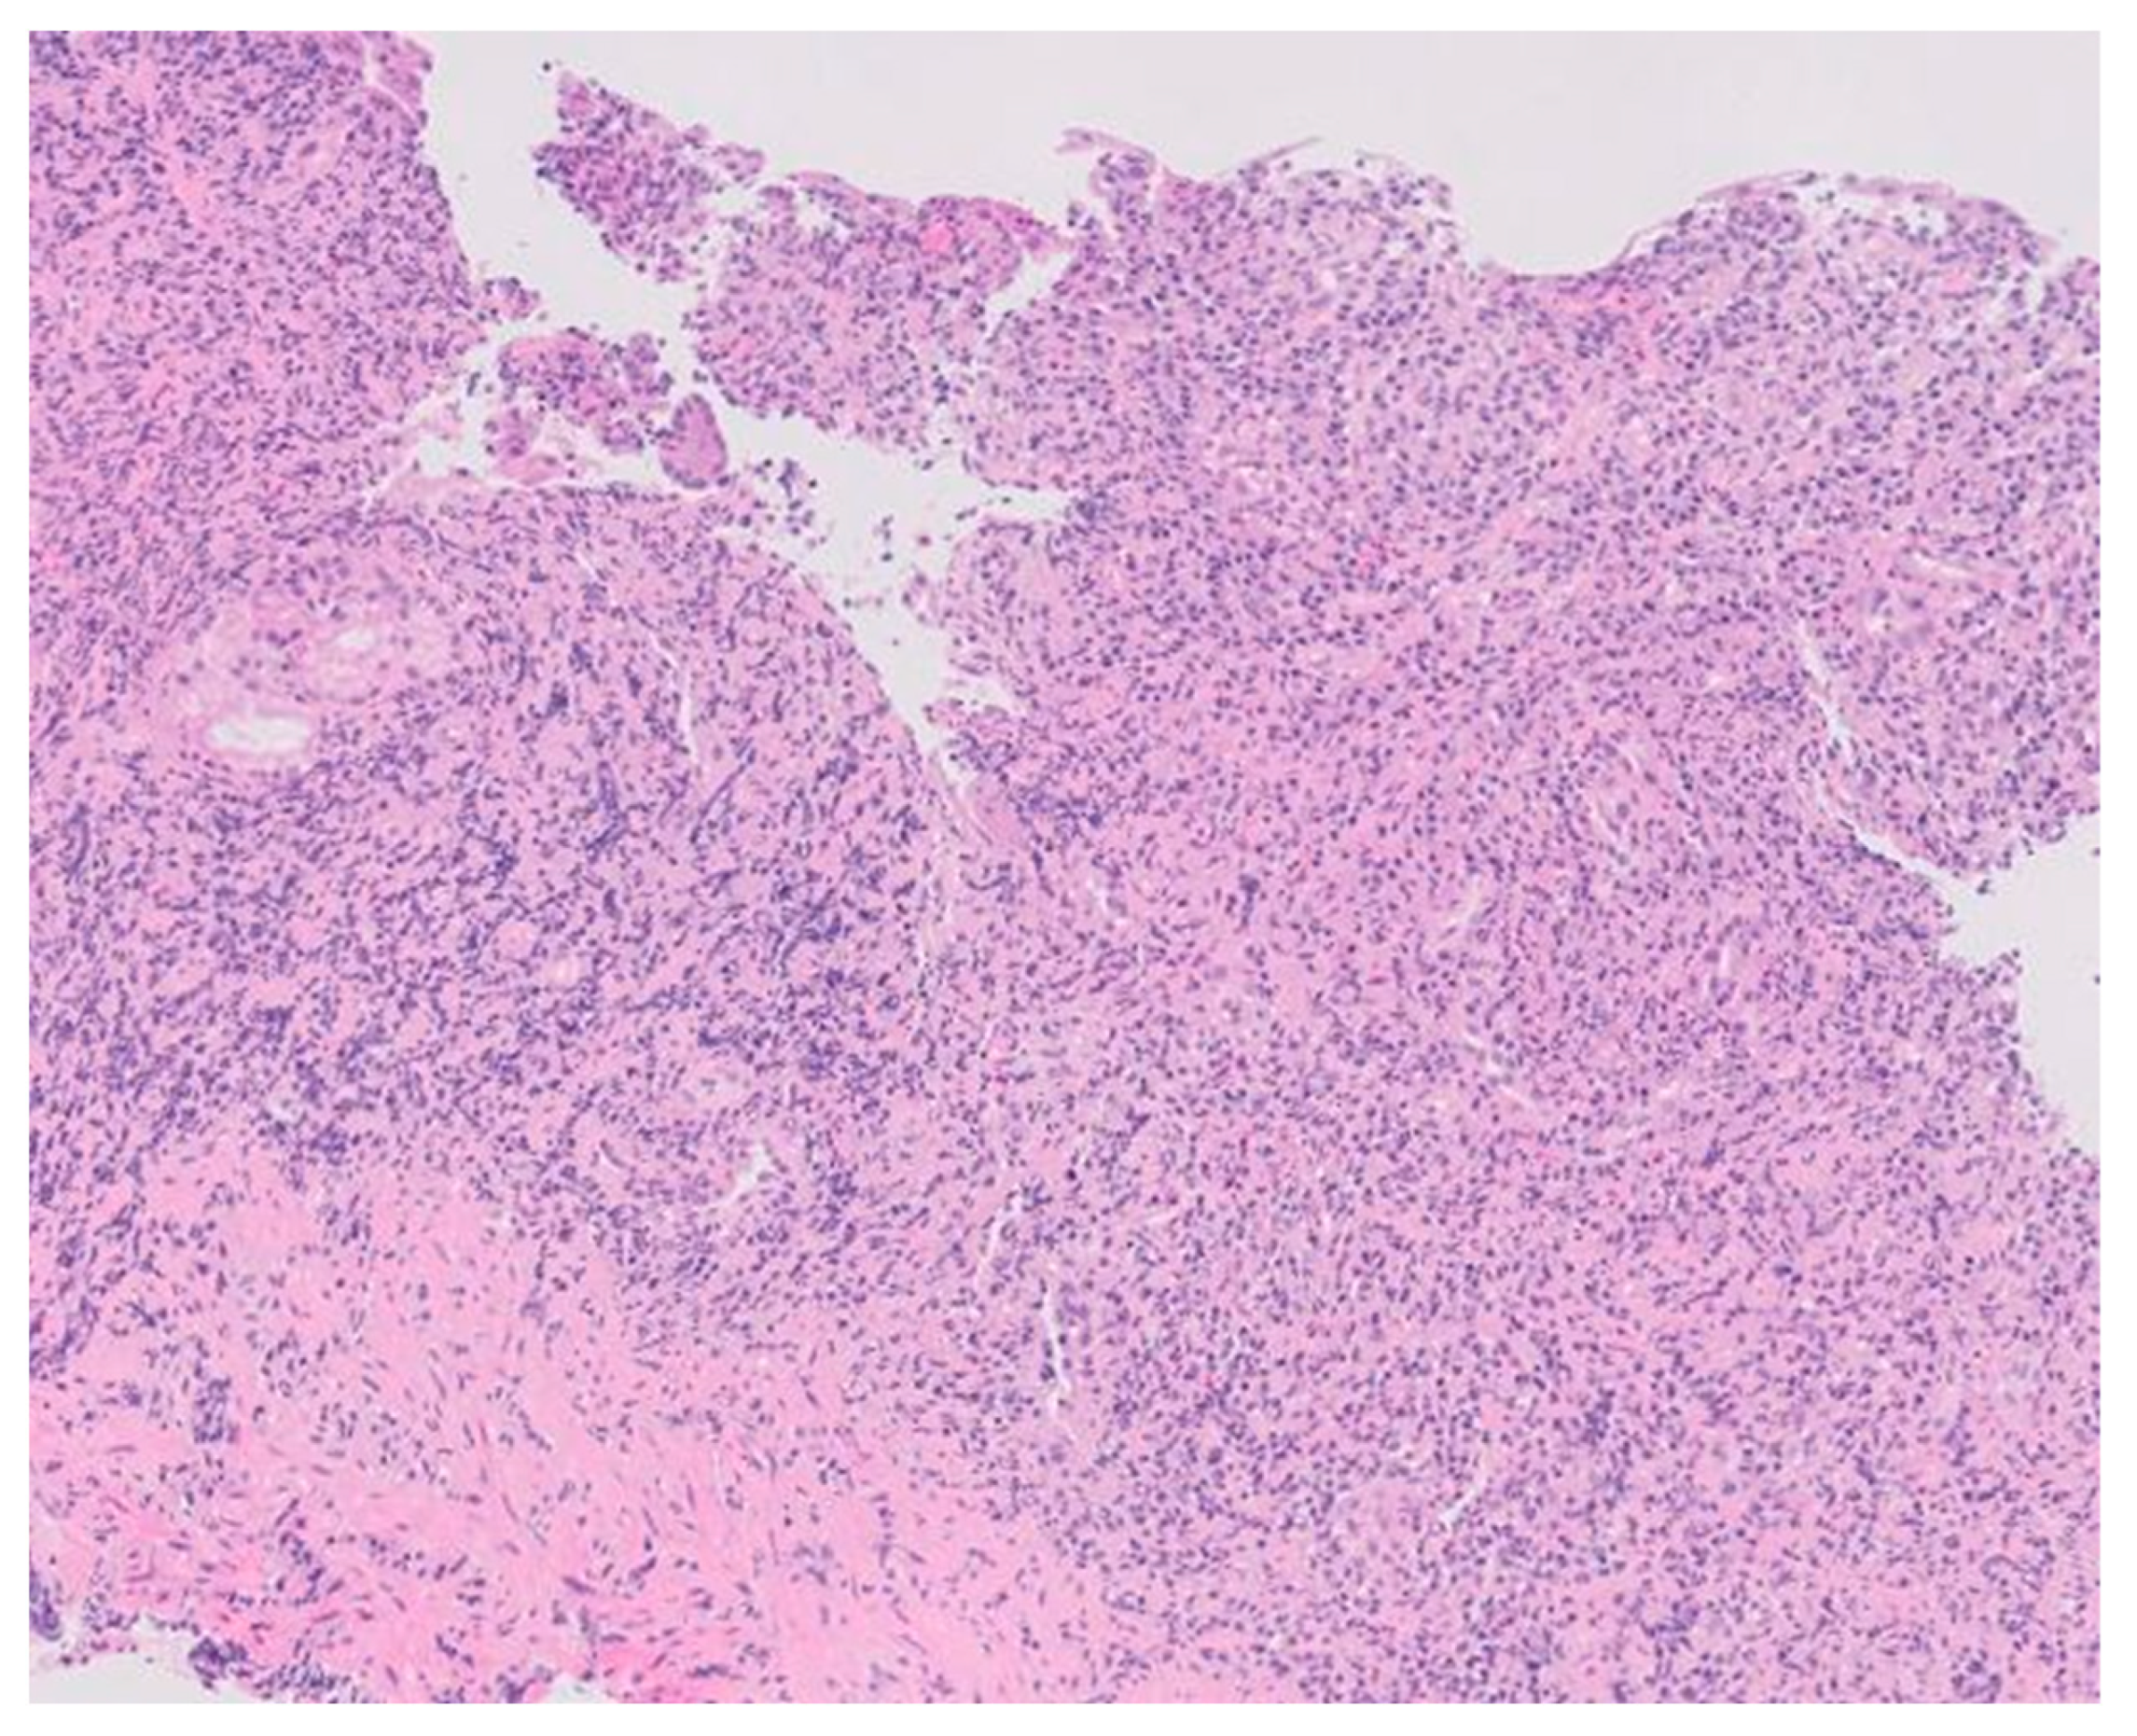

2. Case Description